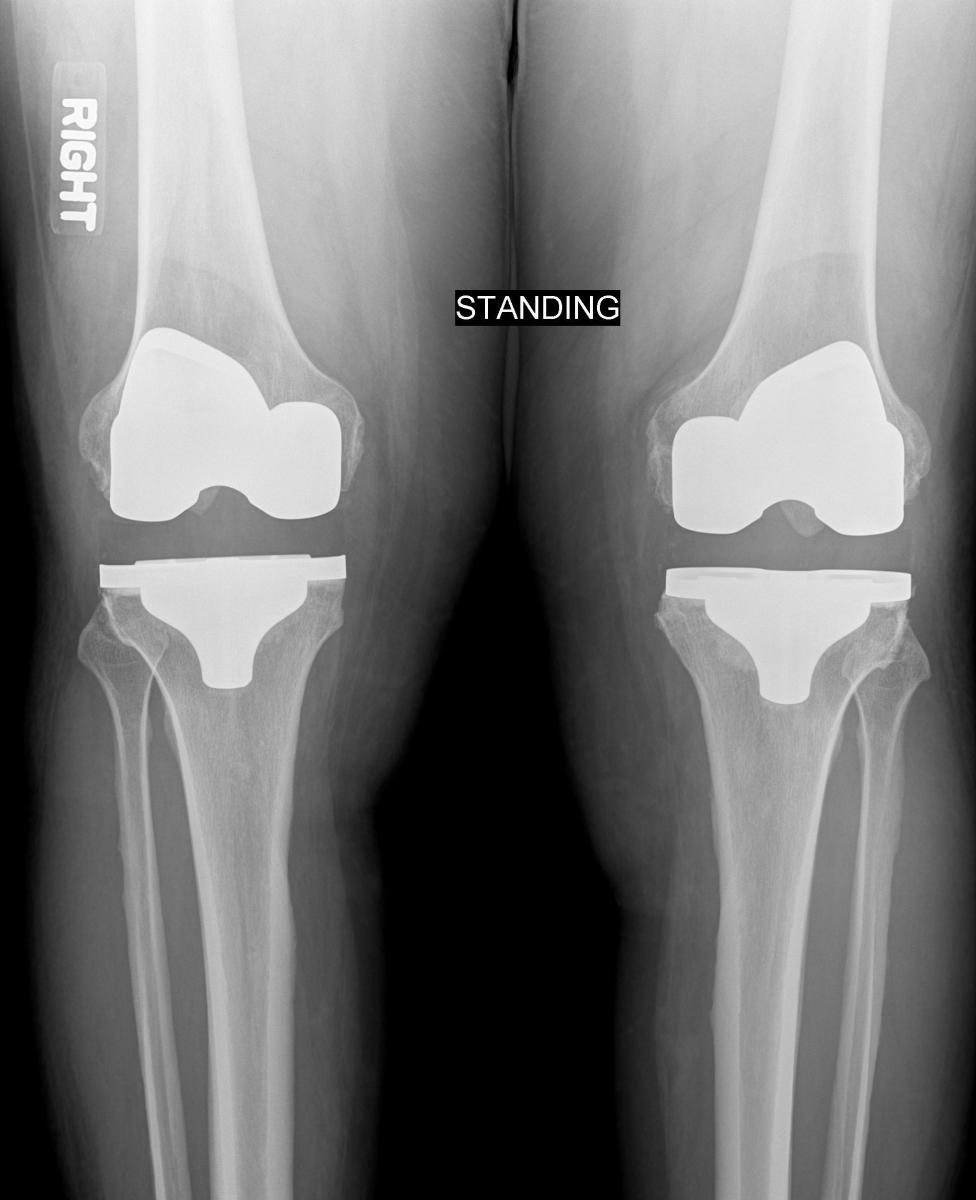

I had the proverbial "bone-on-bone" osteoarthritis knee damage for nearly 20 years. Pain, limited mobility and time convinced me that bilateral knee replacement surgery was smart thing to do. I selected a great team – a highly experienced orthopedist, a very smart internist/hospitalist, a great hospital and physical therapy department and a home physical therapist. I underwent uneventful and expedient surgery (was on the operating table for 2 hours). I awoke in the recovery room, disoriented and mumbling incoherent curses. However within hours they had me standing bedside, with two burly therapists holding me up on my two new magic legs (like Lieutenant Dan) - I felt like a marionette, but I had no pain. I knew immediately, this was a good move. I joined the chorus of other inmate knee replacers in proclaiming, "Damn, I should have done this years ago".

My knee OA dates back to my high school football knee injury and meniscal removal and has been x-ray bad since 1992. Hence, I've had nearly 20 years of compensating for structural damage and adopted some very funky ways of walking, using stairs and getting around. One of the untold post-operative challenges was UN-learn these protective but awkward habits. Again, PT Pam was there to teach and guide as I figured out how move, climb and two step like normal folk.